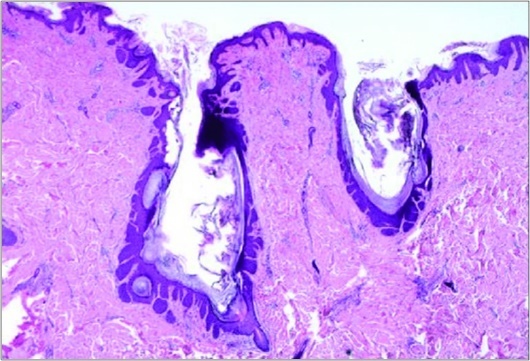

A cogent tissue specimen demonstrates typical features of comedones as follicular ostia distended and impacted with keratin. Significant histological manifestations are the occurrence of enlarged, grouped, distended follicular ostia demonstrating an absence of hair shafts along with impaction of laminated keratin. Base of the follicular invaginations may or may not delineate singular, rudimentary glandular structures. Miniature cysts, cystic invaginations and occasional enlarged cysts can be encountered. Cystic articulations are diverse and preponderantly layered by keratinizing, stratified squamous epithelium. Hyperkeratosis or epidermolytic hyperkeratosis and acanthosis of superimposed epidermis can concur although the lesion is devoid of parakeratosis or dyskeratosis5, 6.

Nevus comedonicus demonstrates immune reactivity to cytokeratin, simulating the expression of normal cutaneous surfaces. Generally encountered within the granular epidermal layer, immune reactivity for filaggrin is demonstrable within the entire epidermal thickness of closed comedones, a molecular which can be implicated in the genesis of nevus comedonicus6, 7. Electron microscopy demonstrates an enhanced quantification of Langerhans cells, numerous kerato-hyaline granules along with an abundance of tonofilaments within upper portion of stratum spinosum. Incompletely differentiated arrector pili muscles are impacted with intracellular glycogen particles6, 7. Figure 1, Figure 2, Figure 3, Figure 4, Figure 5, Figure 6, Figure 7, Figure 8, Figure 9, Figure 10.

Figure 3.Nevus comedonicus with aggregated follicular ostia, lamellated keratin, hyperkeratotic stratified squamous epithelial lining and an attenuated superimposed epithelium12.

Figure 4.Nevus comedonicus with distended follicular ostia, keratin accumulation, hyperkeratotic epithelial lining and intervening loose fibro-connective tissue13.